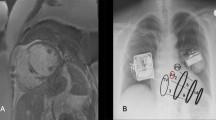

Late gadolinium—enhanced cardiac MRI

Cardiovascular magnetic resonance imaging was performed as described by Maffesanti et al.28 Briefly, patients (5 for Group A and 20 for Group B) were scanned using a 1.5 T scanner (SIGNA, GE Medical Systems, USA) equipped with standard torso coil. Short-axis late gadolinium enhancement (LGE) images were obtained 7–12 min after the intravenous bolus injection of gadolinium (0.2 mmol/kg body weight). Scans were subsequently analyzed via CVI42 v.5.11.2. Each short-axis slice was subdivided into the 16 angular sectors, according to the AHA standard and the local scar burden was expressed as the percent of grey area per subregion. The resulting colormaps were converted into nine segments values by weighted mean based on segment area. The nine segment colormaps were post-processed as described below.

Electro-mechanical mapping

The 3D electro-mechanical mapping system NOGA XP (Biosense Webster, Inc., Irvine, CA, USA) allows simultaneous measurement of local electrical activity and mechanical motion of myocardial tissue. The data are generated by electro-magnetic tracking of a miniaturized sensor located at the tip of the mapping catheter (NOGAStar, Biosense Webster Inc., Irvine, CA, USA), as described in detail previously39. Internal standardized NOGA-algorithms identified and eliminated points with unstable wall contact and inappropriate rhythm or wall movement.